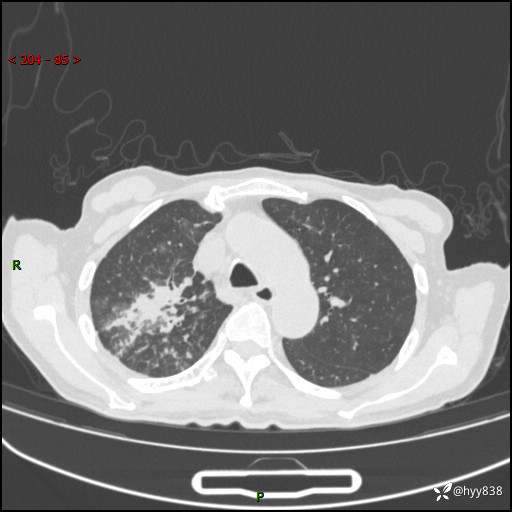

第一次胸部CT检查